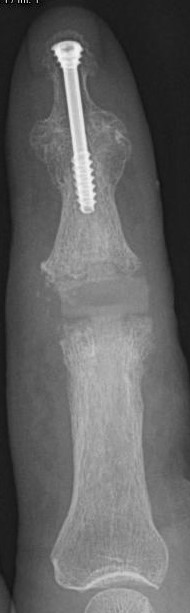

Die Röntgenbilder zeigen die implantierte Prothese im Zeigefingermittelgelenk bei gleichzeitiger Versteifung des Endgelenkes mit Schraube.